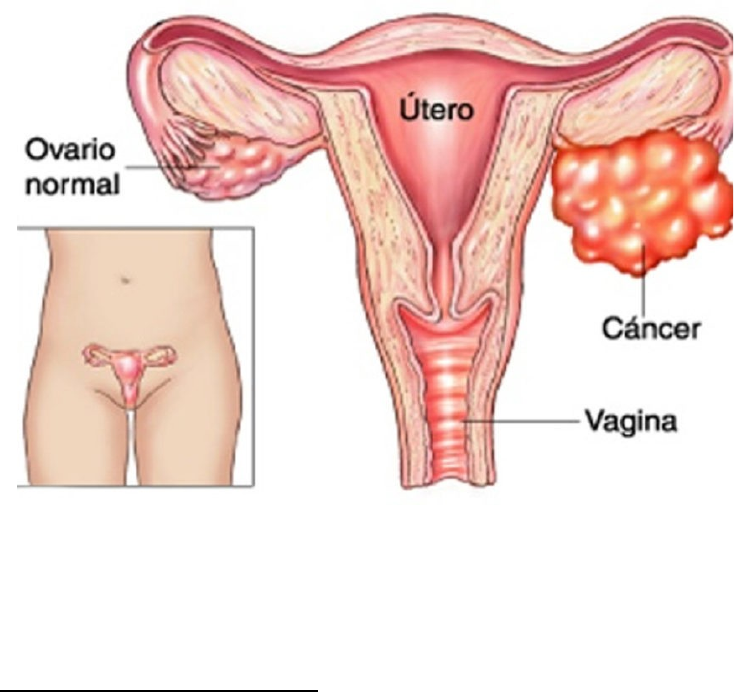

Ooforectomía laparoscópica presentando las tijeras HARMONIC ACE®+7 con hemostasia avanzada

Ooforectomía laparoscópica presentando las tijeras HARMONIC ACE®+7 con hemostasia avanzada

Ooforectomía Laparoscópica Care Guide Information En Espanol12 abril 2025

ooforectomia by edna.rdza on emaze12 abril 2025

Ooforectomía •12 abril 2025